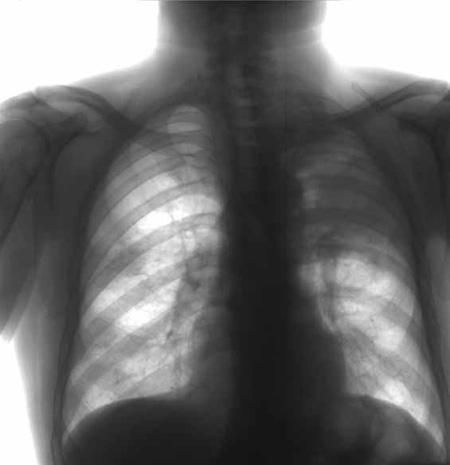

Это вид туберкулеза, при котором в легких на месте разрушенной ткани образуются полости. Заболевание может возникать при наличии другой формы туберкулеза легких, в основном - инфильтративной.